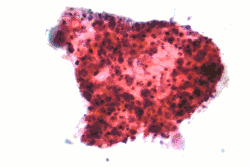

| Micrograph of a squamous carcinoma, a type of non-small-cell lung carcinoma, FNA specimen, Pap stain. | |